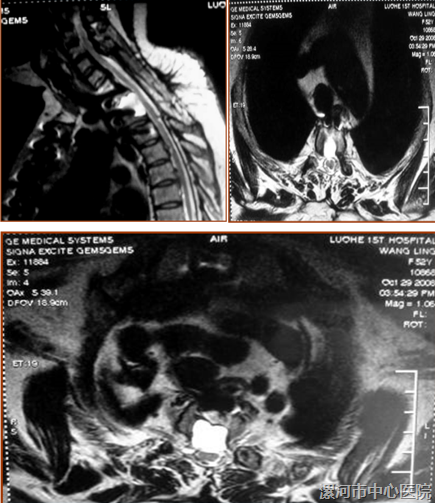

术后影像学检查

术后随访

患者四肢肌力正常Ⅴ级,肌张力无异常,感觉障碍消失。

复查MRI:T1~2,脊髓向前方漂移,前后脑脊液通畅,压迫解除;在硬脊膜前方形成一个封闭的囊腔。